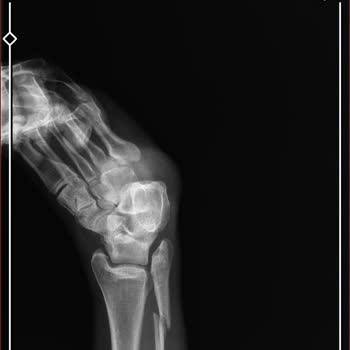

Adana Medical Park Hastanesinde Dr. C*** Özkan ayak ameliyatımı yaptı ve ayağım eskisinden çok daha kötü oldu. Ameliyat esnasında ayaktaki dokulara zarar verdiği için ayağımda his kaybı oluştu. 2 yıl geçmesine rağmen ayağa kalkmakta ve yürümekte çok zorlanıyorum. Bu doktor da hastane yönetimi de mad...